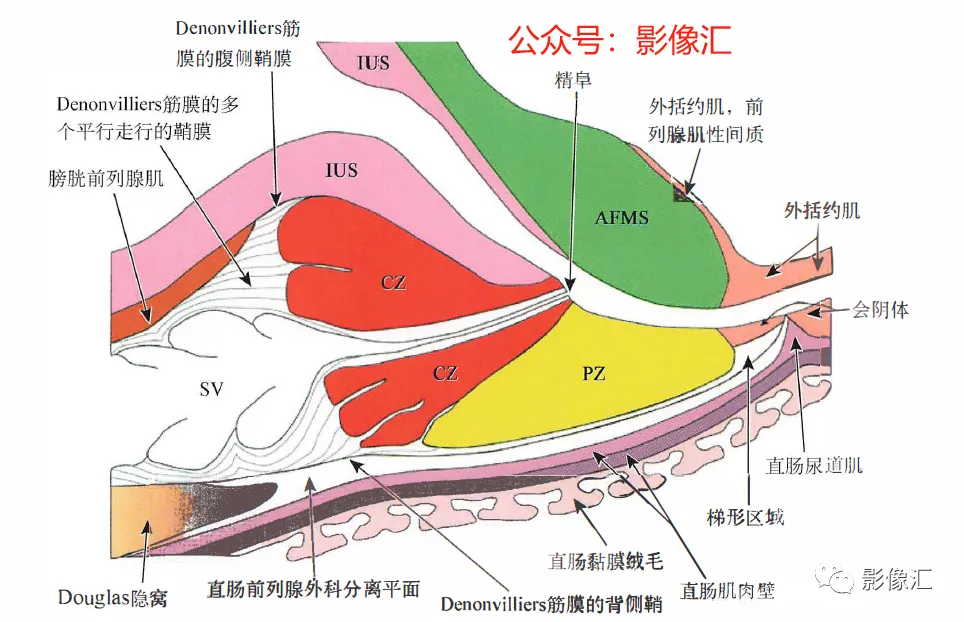

上图,前列腺中线正中矢状切面,显示中央带(CZ)、外周带(PZ)和前列腺肌性间质(AFMS)。注意在CZ底部的精囊喙水平缺少前列腺包膜。Denonvilliers筋膜由多个平行走行的鞘组成,头尾走行。在组织学上,其具有平滑肌纤维,血管和神经的纤维弹性结缔组织。在其侧缘,与Farabeuf骶骨-直肠-生殖-膀胱耻骨筋膜的外侧鞘及膀胱输精管动脉的横向隔膜融合。直肠-前列腺手术分离沿形成Denonvilliers筋膜的鞘复合体背侧进行操作。Denonvilliers筋膜是一层疏松的结缔组织。

AFMS:前列腺肌性间质;CZ:中央带;PZ:外周带;SV:精囊;IUS:尿道内括约肌。

根据示意图可显示五个筋膜(图2.16和图2.17)。上图,前列腺中线正中矢状切面,显示中央带(CZ)、外周带(PZ)和前列腺肌性间质(AFMS)。注意在CZ底部的精囊喙水平缺少前列腺包膜。Denonvilliers筋膜由多个平行走行的鞘组成,头尾走行。在组织学上,其具有平滑肌纤维,血管和神经的纤维弹性结缔组织。在其侧缘,与Farabeuf骶骨-直肠-生殖-膀胱耻骨筋膜的外侧鞘及膀胱输精管动脉的横向隔膜融合。直肠-前列腺手术分离沿形成Denonvilliers筋膜的鞘复合体背侧进行操作。Denonvilliers筋膜是一层疏松的结缔组织。

AFMS:前列腺肌性间质;CZ:中央带;PZ:外周带;SV:精囊;IUS尿道内括约肌。两个矢状面走行筋膜:Farabeuf骶骨-直肠-生殖-膀胱-耻骨鞘(左右各一);三个横轴面走行筋膜:脐-膀胱前筋膜;“生殖动脉隔”;直肠中动脉的隔(Septum of the mid-hae-morrhoiclal artery)。在前列腺,这些鞘也被称为“Retzius前列腺周围筋膜”“前列腺周围筋膜”“前列腺侧带”,或者最近称为“盆内筋膜腹侧面” 。这些筋膜覆盖腺体的侧面和腹侧,在腹侧与前纤维肌性间质(AFMS)融合。供血血管和支配神经在这些鞘内走行。一旦解剖前列腺后部或直肠前平面,这些鞘在前列腺的两侧形成手术分离平面。前列腺“本身”不具有包膜结构;所谓的包膜只是腺样间质聚集所致,而且个体间变异度很大,同时在某些点上并不存在,从而构成McNeal所述的解剖薄弱区域。因此,从实际的角度来看,我们认为虽然前列腺没有自己的包膜结构,但其确实有三个“假包膜":